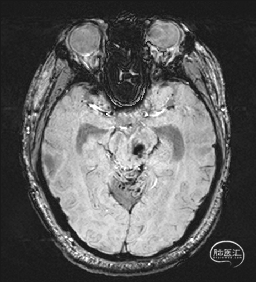

术前DTI检查

根据MRI及DTI显示,只有在丘脑与上丘之间的点(dot)进入病变才可能在切除病变时最大程度保护神经功能,由于上述原因,该“点”在术中显露极其困难,虽有导航指引,电生理监测的条件下,对术者的耐心、技术、经验及体能依然是极大的挑战;

术前详细的磁共振检查,包括平扫增强,SWI及DTI,可以规划出手术最适宜的路径及切入点;